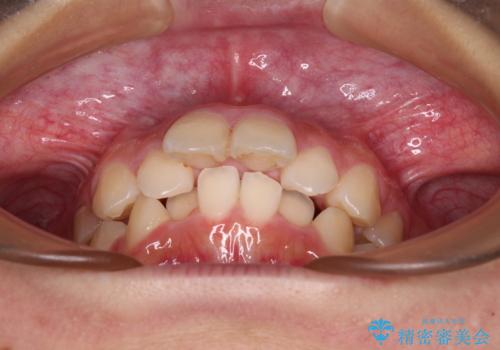

- 下唇の上に乗っかってしまうくらい前歯が飛び出していることを気にして来院された患者様です。

唇を閉じようとするとオトガイ部に力が入ってしまい、うまく閉じることができない状態であったため、上下左右の第一小臼歯4本を抜歯して、ワイヤー装置にて矯正治療を行うこととしました。